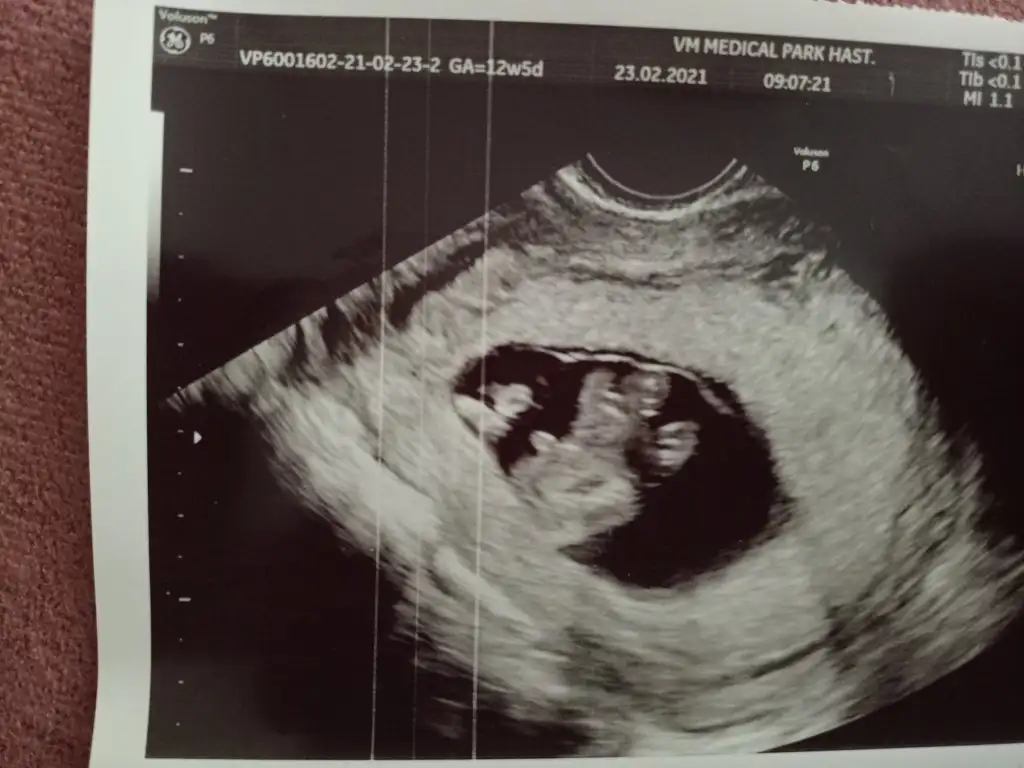

Kızlar Merhaba, bugün 12+5 ve ikili tarama için ultrason yapıldı. CRL 6.6 haftası ile uyumluymuş ancak ense kalınlığı 2.3 çıktı. Doktorum sınırın 2.5 olduğunu ve sınıra yakın olduğu için Down Sendromu riski içerdiğini söyledi. Nipt önerdi ancak bunun için kan tahlilinin de sonucunu bekliyorum. 26 yaşıma yeni girdim, hep sağlıklı beslenirim, alkol ve sigara kullanmıyorum. Yani risk grubunda değilim bu yüzden telaşlıda değilim ama yine de moralim bozuldu. Benzeri bir durum ile karşılaşan oldu mu?